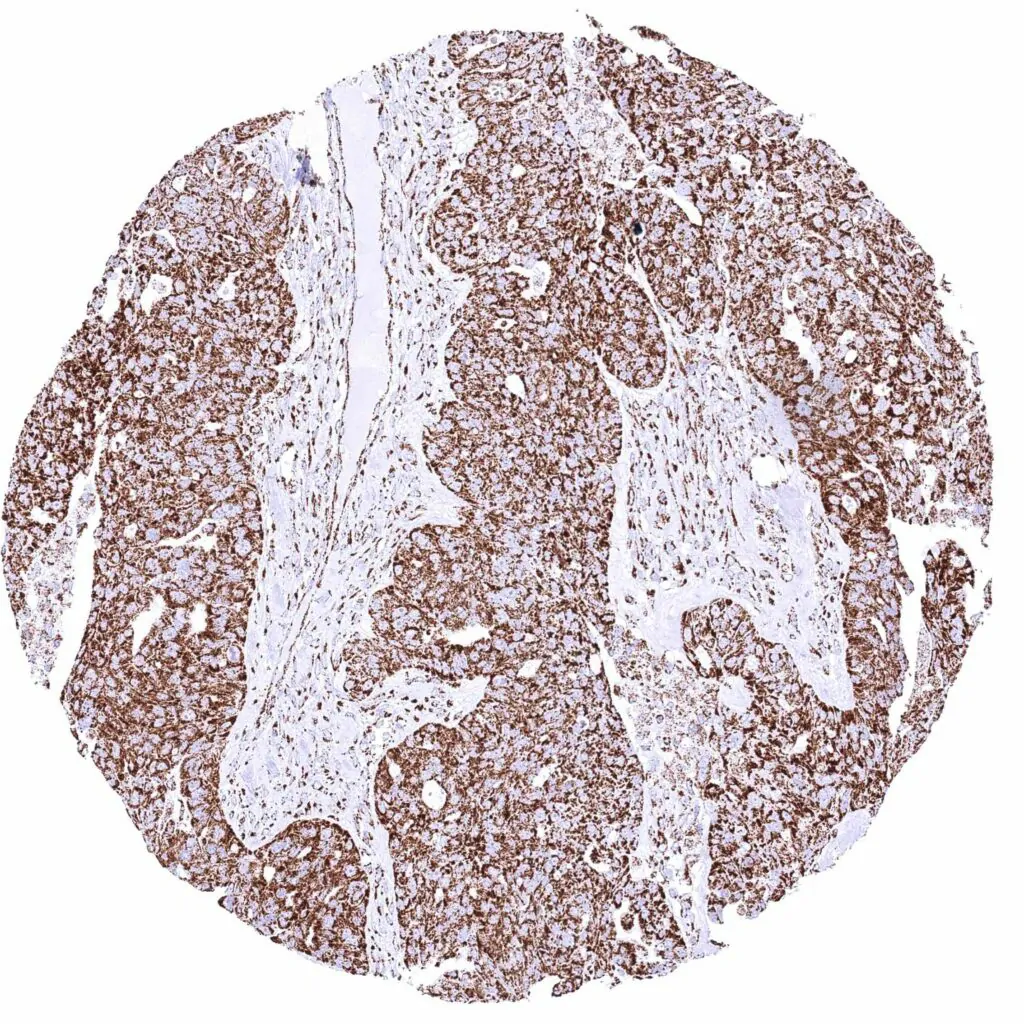

Colon – Colorectal adenocarcinoma with strong cytoplasmic ATP5J staining of all tumor cells.